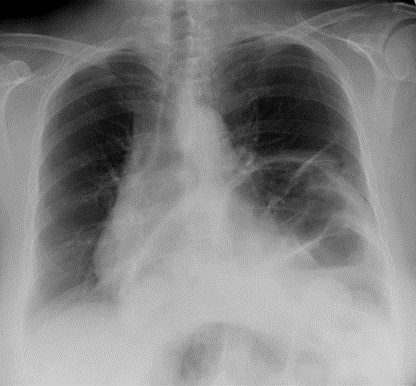

Pleural Effusion

____ is defined as the accumulation of fluid in the pleural space.

____ is seen in the costophrenic angle only (seen on Lat. views), unless it is a high level ___ (Lat. and PA views).

Subpulmonic effusion

____ is an accumulation of fluid between the lung base and diaphragm. It does not blunt the costophrenic angles.